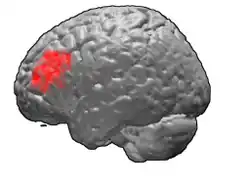

Brodmann area 46, or BA46, is part of the frontal cortex in the human brain. It is between BA10 and BA45.

BA46 is known as middle frontal area 46. In the human brain it occupies approximately the middle third of the middle frontal gyrus and the most rostral portion of the inferior frontal gyrus. Brodmann area 46 roughly corresponds with the dorsolateral prefrontal cortex (DLPFC), although the borders of area 46 are based on cytoarchitecture rather than function. The DLPFC also encompasses part of granular frontal area 9, directly adjacent on the dorsal surface of the cortex.

Image

Animation. -

Frontal view. -

Lateral view.